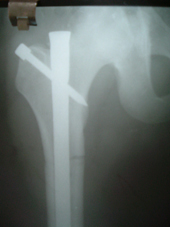

| Fracture Femur |

Interlocking nailing femur |